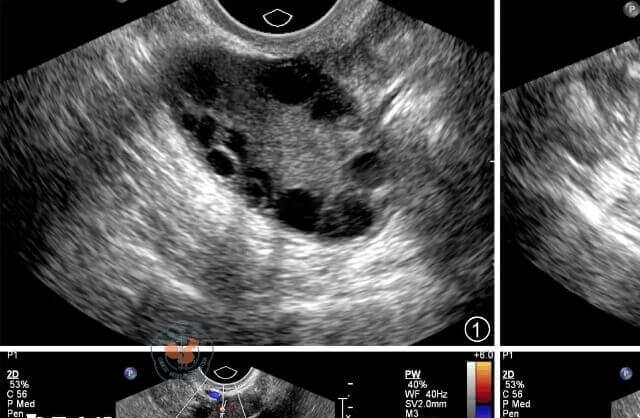

女性优势卵泡的大小是有一定的标准,如果卵泡长得过大或是过小,就要去医院做卵泡监测了解卵泡,结合中西医用药方式缓解卵泡的情况。那么,究竟是什么原因导致女性生育后检查卵巢挤满小卵泡,如下所示:

1、多囊卵巢综合征

由于卵巢发生了多囊性改变,比如临床多囊卵巢综合征的情况下,就会使双侧卵巢内有12个以上的卵泡,并且还会出现雄性激素增高,还会出现不排卵的情况,在临床上经过系统的治疗,也会改善相应的症状,达到怀孕的目的。

2、卵泡早期发育阶段

在月经周期的卵泡早期,卵巢内会有多个小卵泡开始发育,通常只有一个会成为优势卵泡继续发育成熟并排卵,其余卵泡会闭锁退化。如果检查时间恰逢这个阶段,可能会看到卵巢内有较多小卵泡,这是正常的生理现象。